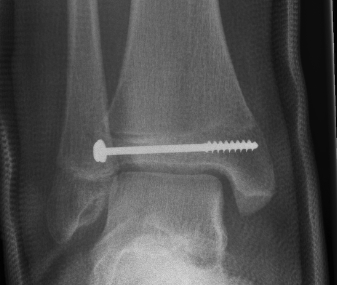

Triplanar Fracture

Definition

- fracture in coronal, sagittal and transverse planes

- 2, 3 or 4 part

Management

ORIF

- > 2mm displacement

- usually anterolateral approach to reduce

- epiphyseal medial-lateral screw

- metaphyseal AP screw